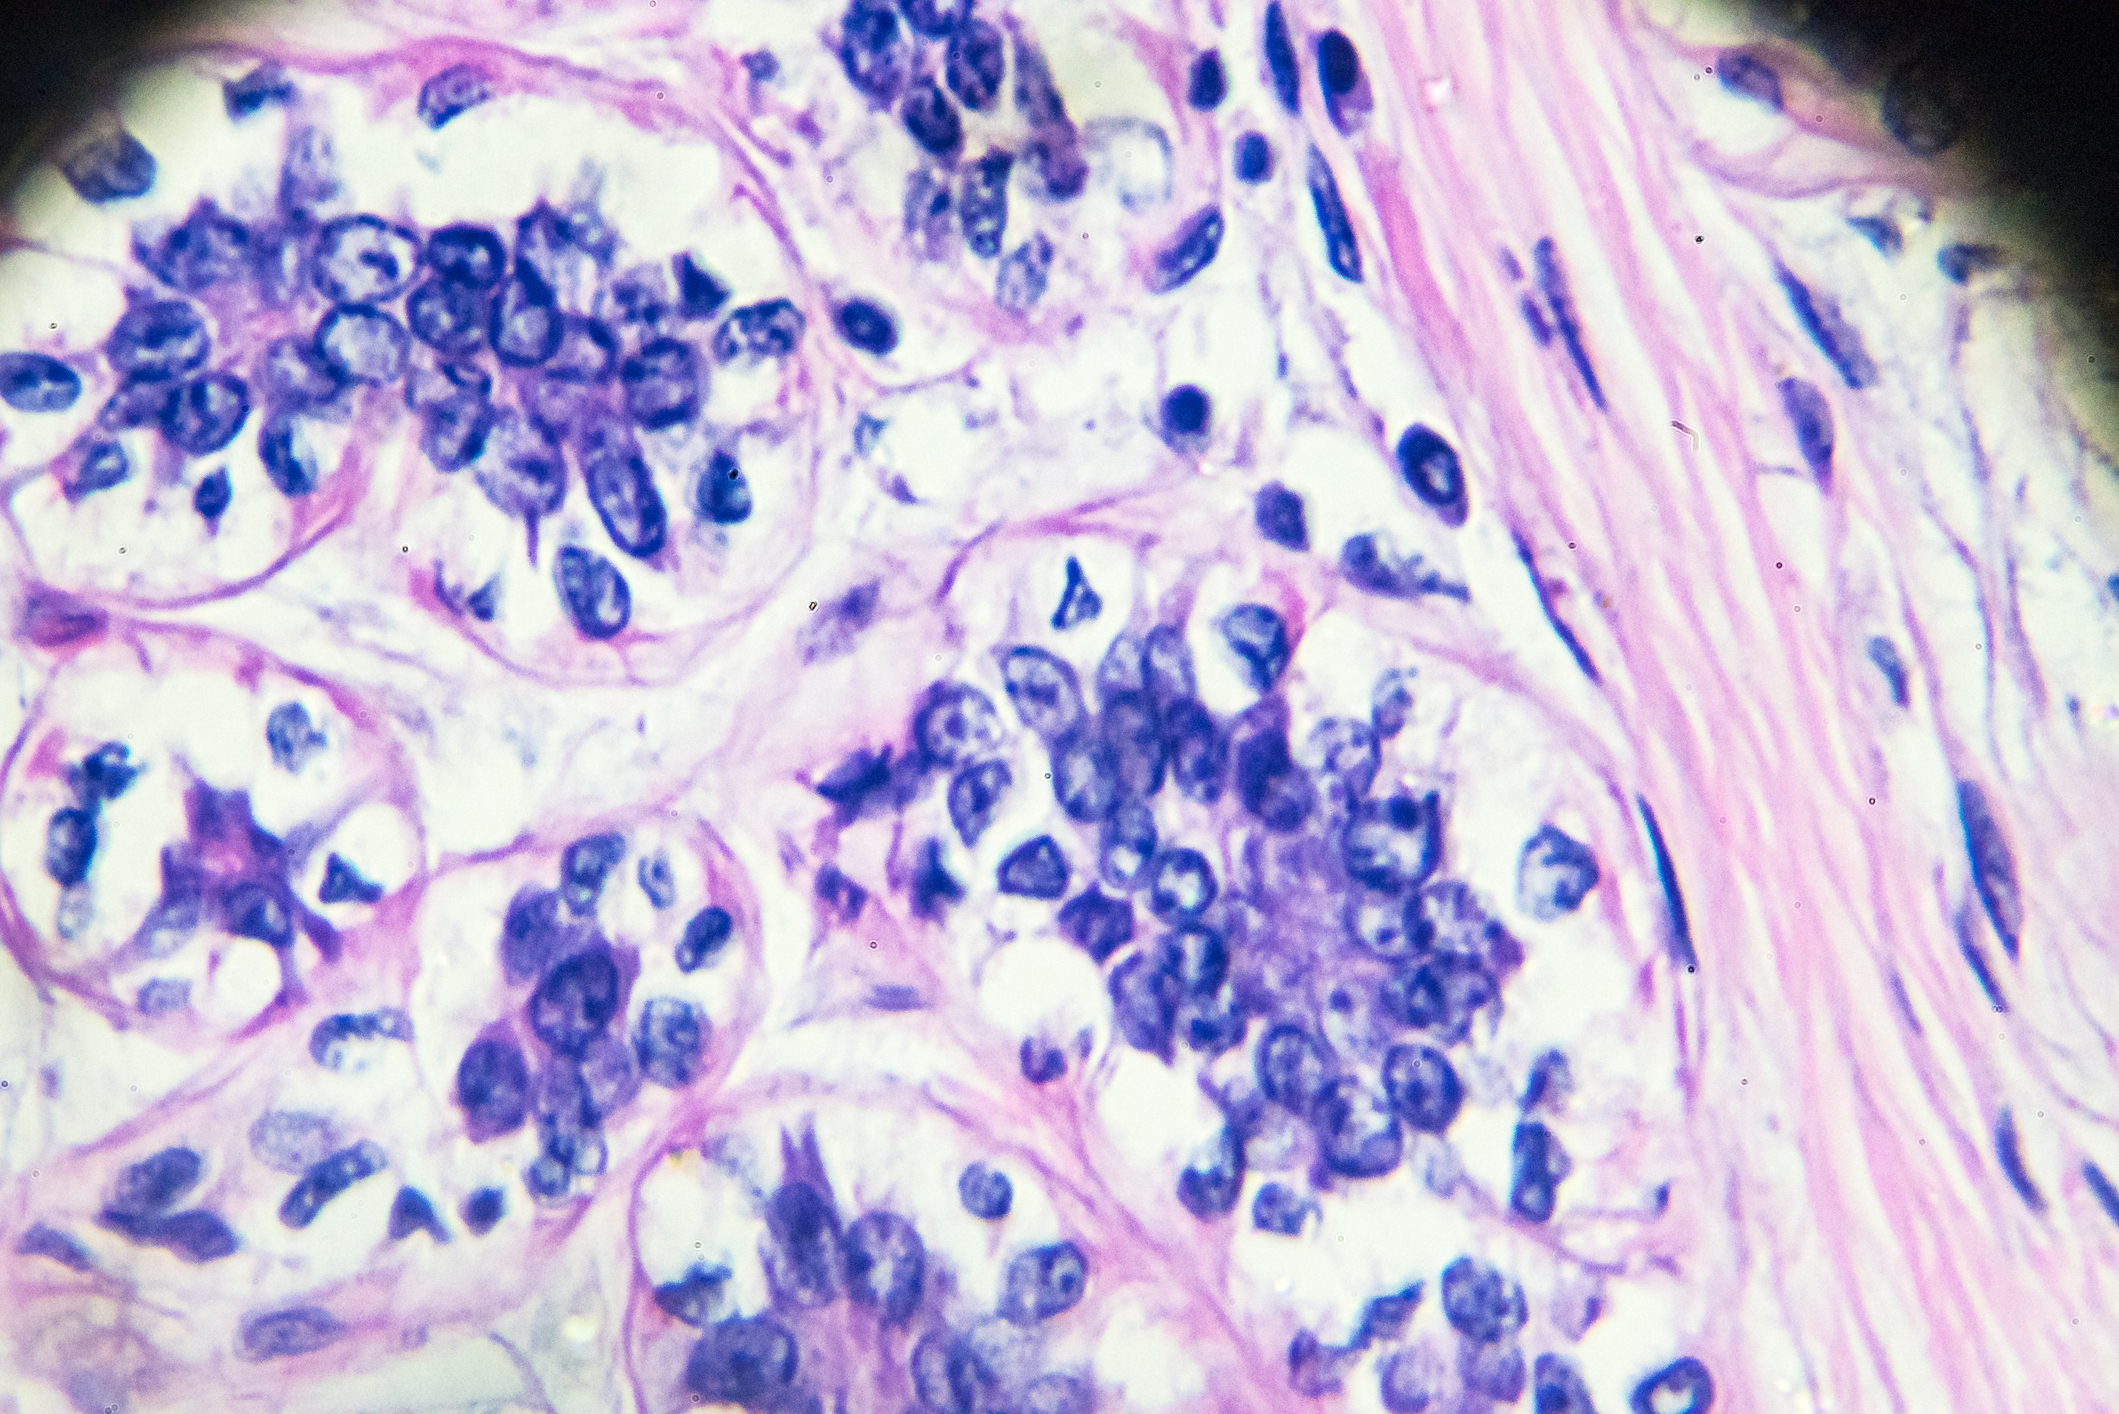

The most common types of male breast cancer include: early breast cancer, invasive ductal carcinoma, Paget’s disease of the nipple, inflammatory breast cancer, ductal carcinoma in situ (DCIS) and lobular carcinoma in situ (LCIS).